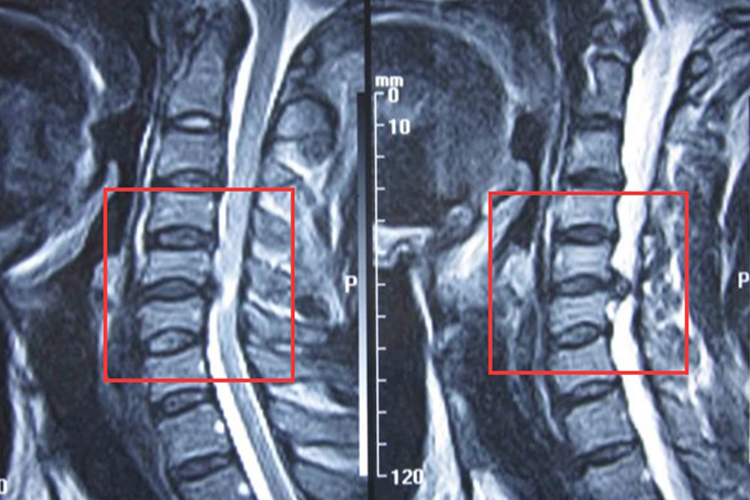

3、腰椎间盘突出症:是由于腰椎间盘各部分发生退行性改变后,在外力因素的作用下,椎间盘的纤维环破裂,导致相邻脊神经根遭受刺激或压迫,从而产生腰部疼痛,一侧下肢或双下肢麻木、疼痛等一系列临床症状。通过卧床休息、牵引、理疗及药物治疗等保守治疗,多数患者症状可得到缓解。但若压迫严重,出现持续性腰腿痛、肌力减退等症状,可能需手术治疗,如椎间孔镜微创手术,术后恢复效果因个体差异而异。